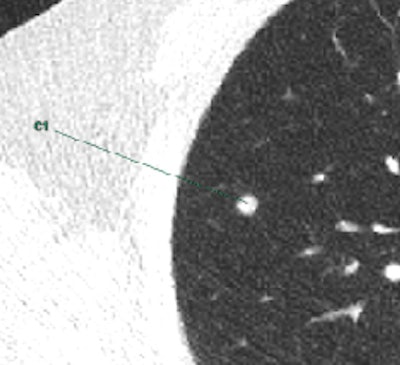

Marking of a CAD-software-detected solid nodule in the right upper lobe in ultralow-radiation-dose CT (0.15 mSv). All images courtesy of Dr. Michael Messerli.Messerli, who won the best oral presentation Cum Laude award for the work at the 2016 annual meeting European Society of Thoracic Imaging (ESTI) in Krakow, Poland, sees two specific diseases where CAD in combination with ultralow-dose CT can improve patient handling.